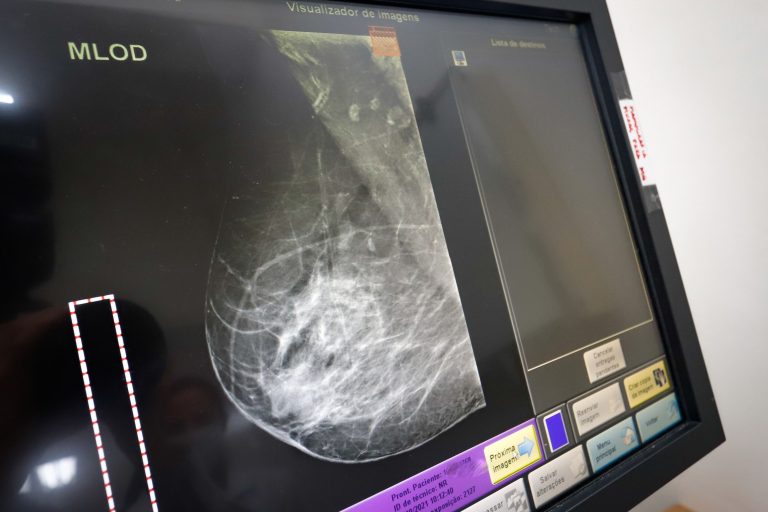

No mês de conscientização sobre o câncer de mama, mamografias e exames gratuitos de rastreamento para detecção da doença serão oferecidos em onze pontos do estado de São Paulo até dezembro, pela ONG Américas Amigas.

A campanha acontece através da unidade móvel da organização, que é equipada com mamógrafo, ultrassom e impressora de filme de exame. Os resultados são entregues em até 2 horas após a realização.